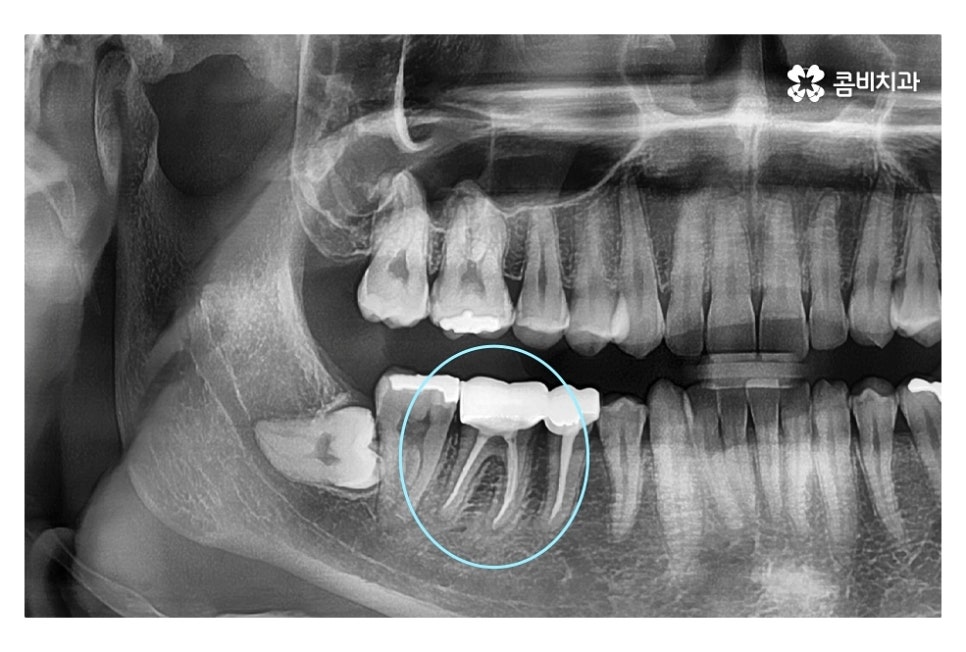

같은 환자분의 사진인데 좌측 치아의 경우 신경치료 후 크라운으로

마무리를 했지만 우측 어금니의 경우 치아의 대부분이

손상이 되어 결국 발치 후 임플란트를 하게 된 사례라고 할 수 있는데요.